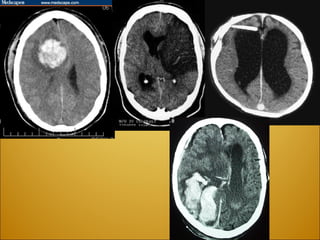

 Acute cerebral contusions Two weeks after injury

Epidural hematoma .  Usually s/p  head trauma . Brief  +LOC, followed by lucid period.  Then drowsy/coma/death . A well-defined  biconvex  collection of blood (arrows) compresses the left cerebral hemisphere. There is inward displacement of the grey-white junction (arrowheads) and slight rightward displacement of the left lateral ventricle.

Subdural hematoma :   a  concave  collection of  venous blood between the dura and the arachnoid   (resulting from tears of the bridging veins that extend from the subarachnoid space to the dural venous sinuses.) Patients with cortical atrophy, such as alcoholics and the elderly, are more susceptible to subdural hematoma formation when undergoing acceleration-deceleration forces during  head trauma .  After 2 weeks, patients are defined as having a chronic subdural hematoma, which appear hypodense on a CT scan.

Large acute subdural hemorrhage  (arrows) revealed by CT scan at the level of the lateral ventricles.  The hemorrhage has resulted in midline shift, with marked compression and displacement of the right ventricle (arrowheads).  Because of the brain distortion and obstruction of CSF outflow, the left lateral ventricle is dilated (wavy arrows).

Right subdural hemorrhage revealed by MRI . The high intensity (white) hemorrhage has dissected under the temporal lobe, and the midline has been displaced to the left. Note the skull fracture overlying the hematoma.

Chronic bilateral subdural hematoma .  This skull X-ray shows areas of calcification adjacent to the inner table of both parietal bones (arrows).  The diagnosis was confirmed by CT.

Subarachnoid hemorrhage :   results from the disruption of subarachnoid vessels presents with  blood in the cerebrospinal fluid .  Not a space occupying lesion, “pero” can lead to increased ICP and acute hydrocephalus Patients may complain of  headache, photophobia, and have mild meningeal signs . Noncontrast CT is diagnostic in most cases (95%) If CT is neg, but clinical suspicion is strong do LP “ Worst HA of my life” “ Thunder-clap HA”  Sudden Onset